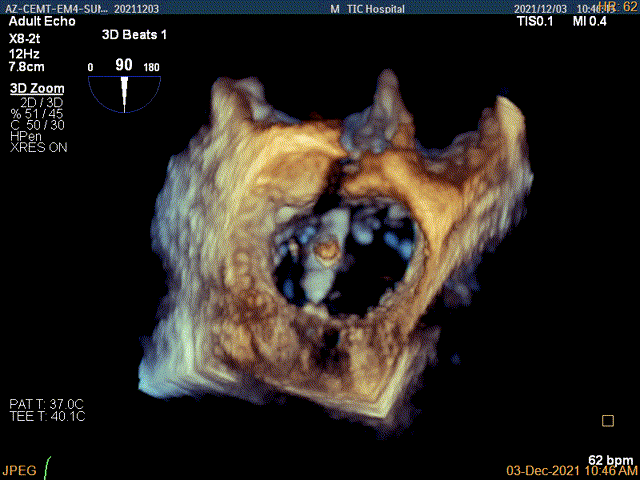

夹子关闭过程中,Color提示1区反流逐渐减少

二尖瓣口平均跨瓣压差:2mmHg

肺静脉血流频谱恢复正向

4Ch验证前后叶抓捕后有典型的bouncing征

x-plane平面测量确认后叶抓捕长度大于6mm